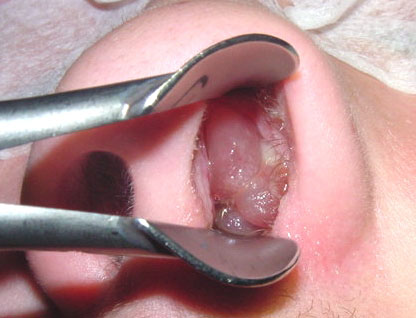

鼻息肉:反反复复长

鼻息肉是发生于鼻腔、鼻窦黏膜的新生物,多于体检时发现。

3.手术指征

鼻息肉首先考虑药物治疗,如鼻用糖皮质激素、鼻腔盐水冲洗等。

药物效果差、难以控制的情况下,才需要手术治疗。而且,术后复发率高,仍需配合药物治疗预防鼻息肉复发。